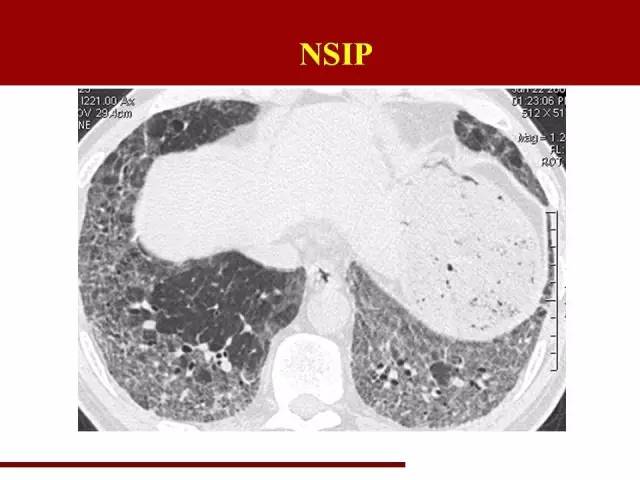

NSIP诊断条件相对放松一些

分布和UIP一致,不同的是磨玻璃阴影多于网格状阴影,可以伴有牵拉性支气管扩张

那么在这里提到两个概念

间质性肺炎的磨玻璃阴影:病理基础为小叶内间质增厚,即肺泡表面的间质发生炎症,覆盖部分肺泡,使肺泡密度增高,形成磨玻璃阴影。在NSIP中,这部分磨玻璃阴影代表着可逆部分,也就是说及时治疗有可能能恢复肺泡功能。因此影像科在报告的时候尽量能把磨玻璃阴影提出来,以便临床进行疾病严重程度评估。

这是NSIP

磨玻璃影比较明显,有可能可以可逆,这部分肺组织的保护很重要

影像科对间质性肺炎的分类的意义大致在此吧